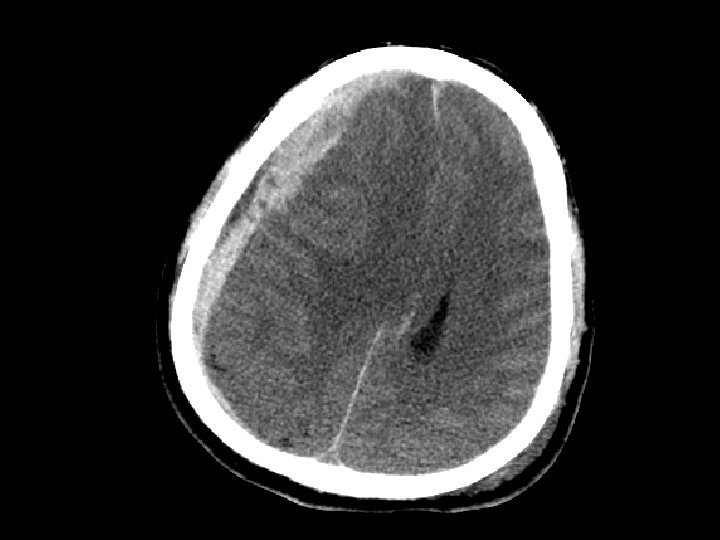

Cerebral Contusion • Bruising to the brain • Most common traumatic finding on CT • Large contusions may have significant bleeding (hemorrhagic contusion or intracerebral hematoma), edema, or cause seizures • Location: Frontal and Temporal lobes – Due to irregularity of the skull base • Treatment: close observation

Subarrachnoid Hemorrhage (SAH) • SAH and contusion are most common injuries on CT after blunt trauma • CT: blood in the sulci and basal cisterns • Often associated with intracranial hematomas • Must consider that the SAH caused the trauma (spontaneous bleed and then fall) • Complications: – Arterial vasospasm: 2 -3 days after injury